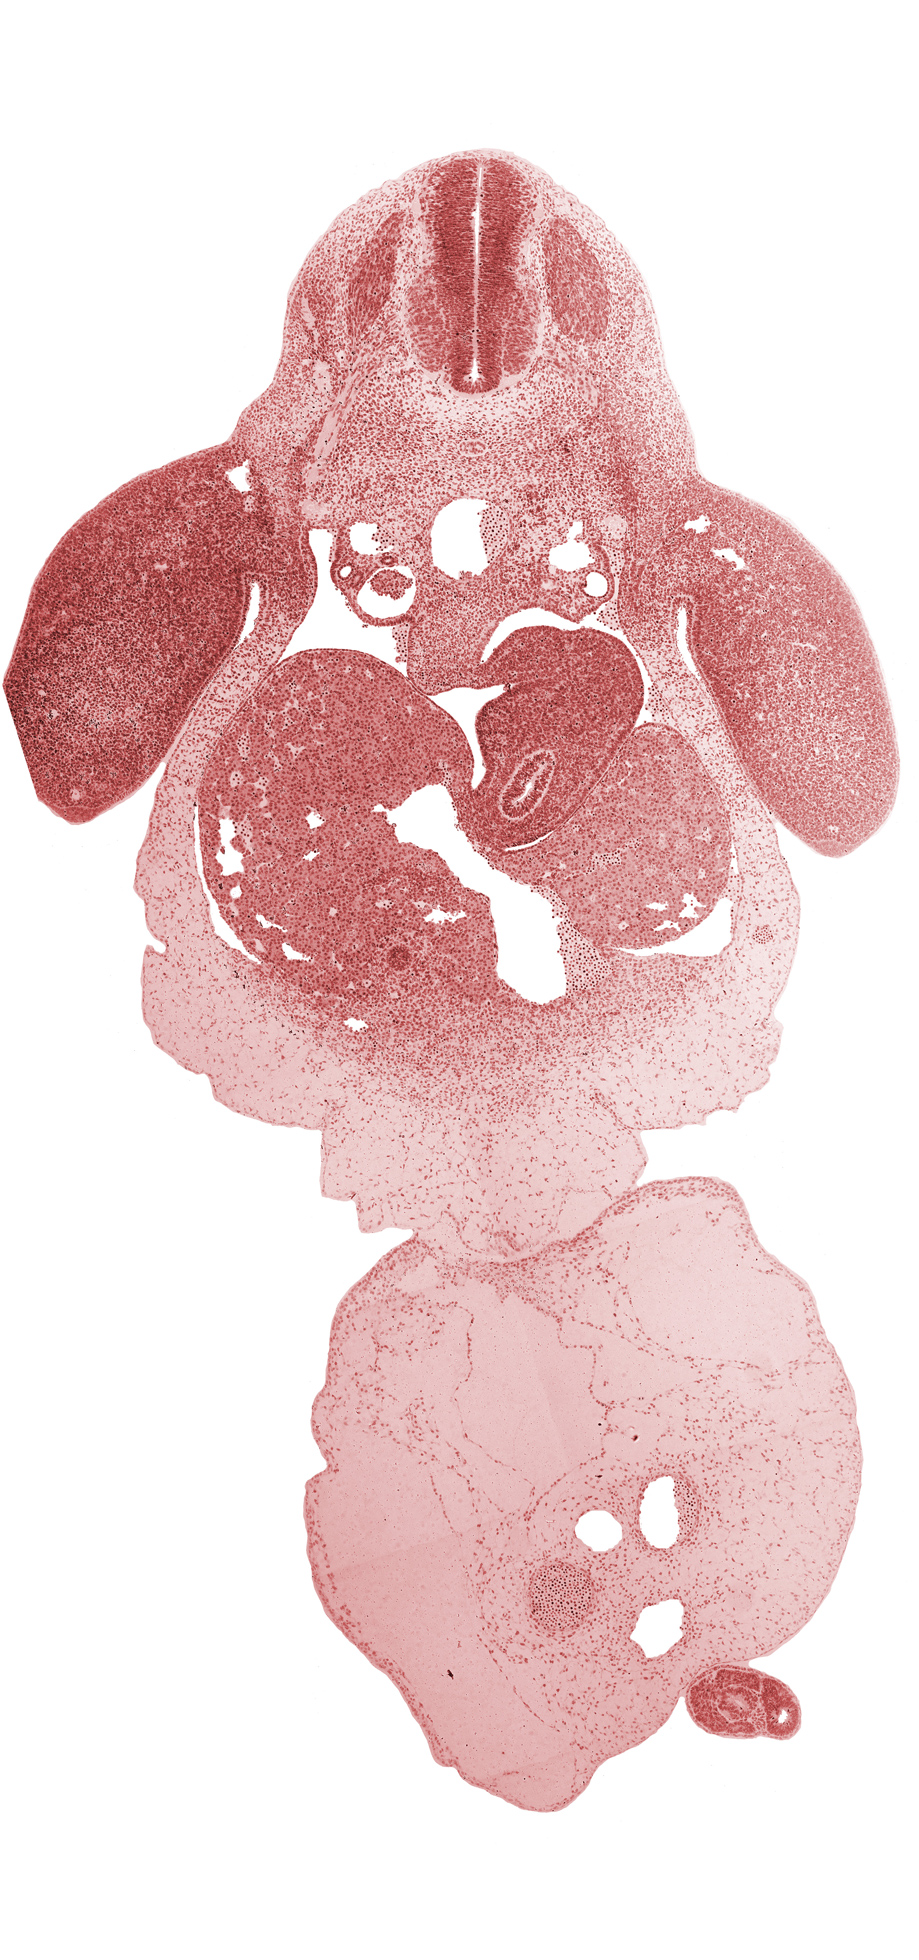

C-8 spinal ganglion, aorta, bile duct, common umbilical vein, dorsal mesentery, dorsal mesogastrium, ductus venosus, left lobe of liver, left umbilical artery, lesser  sac, marginal vein, mesonephric duct, neural canal, neural tube, notochord, post anal gut, postcardinal vein, right lobe of liver, right umbilical artery, sclerotome, septum transversum, spleen primordium, stomach, umbilical coelom, umbilical cord, ventral mesogastrium

Carnegie Embryo #6502   |   Location: 26-05-05

Keywords: C-8 spinal ganglion, aorta, bile duct, common umbilical vein, dorsal mesentery, dorsal mesogastrium, ductus venosus, left lobe of liver, left umbilical artery, lesser sac, marginal vein, mesonephric duct, neural canal, neural tube, notochord, post anal gut, postcardinal vein, right lobe of liver, right umbilical artery, sclerotome, septum transversum, spleen primordium, stomach, umbilical coelom, umbilical cord, ventral mesogastrium